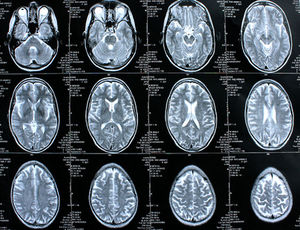

Gehirn im Schnitt: Denken und Sprechen gehören zusammen. Bild: pixelio.de, Rike